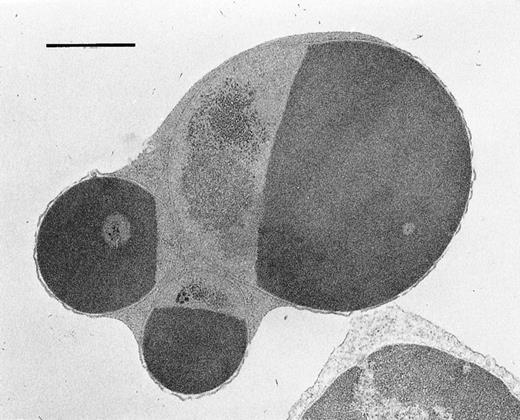

To confirm whether the expressed Fas on hematopoietic progenitor cells is functional or not, we examined the effects of apoptosis-inducing anti-Fas antibody (Jo2) on BM cells in vitro.16 On day 14 after GVHD induction, BM cells were obtained and incubated with 1 μg/mL of Jo2 in vitro. After 18 hours of incubation, the percentage of cells undergoing apoptosis significantly increased in the BM cells from BDF1 mice receiving B6 spleen cells, from 7.25% ± 0.63% to 14.83% ± 2.22% (P < .05) . In contrast, no such an increase was observed in the BM cells from the normal control mice (data not shown). Apoptosis was further confirmed by the electron microscopic feature of cells with chromatin condensation in the presence of plasma membrane integrity (Fig3). To assess the number of functional progenitor cells, a CFU-GM assay was performed using BM cells incubated with Jo2 for 18 hours in vitro (Fig 4). CFU-GM significantly decreased after treatment with Jo2 in the mice with acute GVHD, but no such effect was observed in the control BDF1 mice or mice with chronic GVHD. These data confirmed that the induced expression of Fas in the hematopoietic cells in acute GVHD was functional in vitro.

Electron microscopic appearance of BM cells after treatment with anti-Fas antibody (Jo2) . Cells were cultured for 18 hours in the presence of Jo2. (Original magnification × 13,500.)